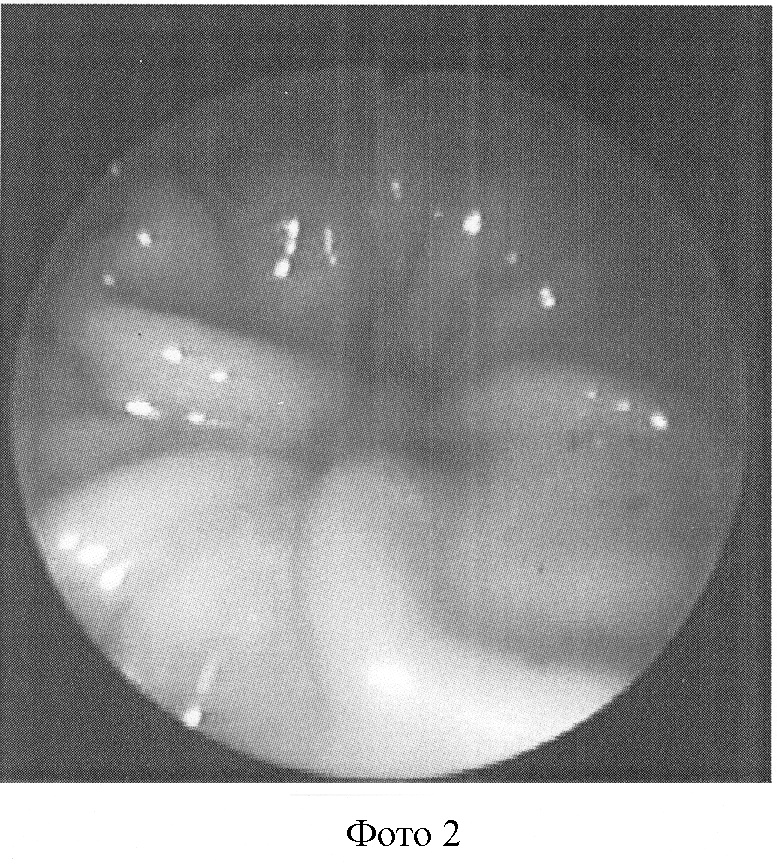

Сущность данного обследования поясняется фотографиями, где:

Фото 1: расслабленное состояние жома.